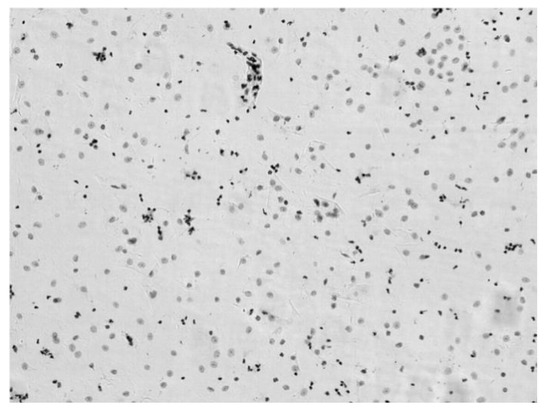

3.1. Pseudo-Color Image Synthesizing and Absorbance Unmixing

3.2. Verification Test of DNA Quantitative Analysis

3.3. The Performance of Cervical Cell Screening